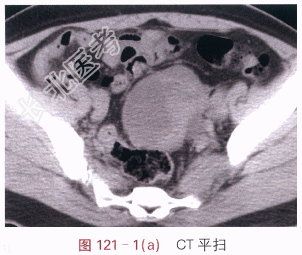

影像学资料如图121-1~图121-3所示。

读片分析:左侧附件区囊实性不规则形肿块,CT增强后实性部分的边缘呈明显强化,中心坏死部分强化不明显,未见肿大淋巴结和腹水征象。多平面重建后可见,左输尿管下段后累及,其中上段积水扩张。